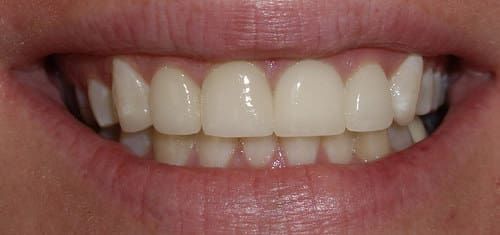

Before / After

From stained or misaligned teeth to a radiant, confident smile, our results speak for themselves. See the difference professional dental treatment can make — and imagine what we can do for you.

Crowns & Bridges